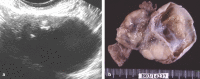

Brenner tumors are rare ovarian neoplasms composed of ovarian transition cells surrounded by dense fibrous tissue. Most of them are small tumors (<2 cm), detected incidentally in asymptomatic women. Its predominantly fibrous content results in relatively low signal on T2 weighted images, establishing differential diagnosis with ovarian fibroma and thecoma. Their imaging features are very similar, the differentiation is based on secondary characteristics, such as signs or symptoms of estrogen excess and the presence of a second ovarian neoplasm, which has been reported in up to 30% of patients with Brenner tumor. Although originally thought to be universally benign, there have been scattered reports in the past decades of borderline and malignant forms of Brenner tumors.